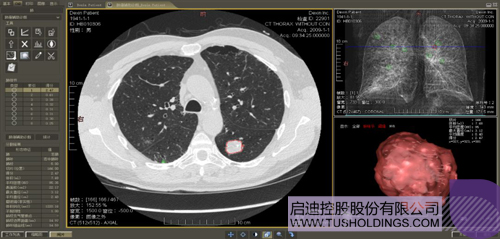

數字肺產品肺癌計算機輔助診斷

醫(yī)療影像智能分析是指運用人工智能技術、計算機視覺技術以及計算幾何技術對醫(yī)療影像進行自動分析,幫助醫(yī)生定位病癥、分析、跟蹤病情,并通過量化數據輔助醫(yī)生做出診斷,目前其旗艦產品“數字肺”已經覆蓋多種肺部疾病的早期檢測、診斷、跟蹤、術前規(guī)劃等完整的醫(yī)療流程。在臨床實踐中,超過80%的醫(yī)療數據來自醫(yī)療影像,這些影像數據通常需要專業(yè)醫(yī)生進行解讀,工作的重復性高、效率偏低。如果能夠運用智能影像分析技術,同時結合臨床表現以及既往病例進行全面分析,那么就可以大幅度提升影像診斷效率和準確性,讓專業(yè)醫(yī)生的寶貴時間集中在復雜病情的診斷和治療等環(huán)節(jié)。

肺動脈栓塞輔助診斷